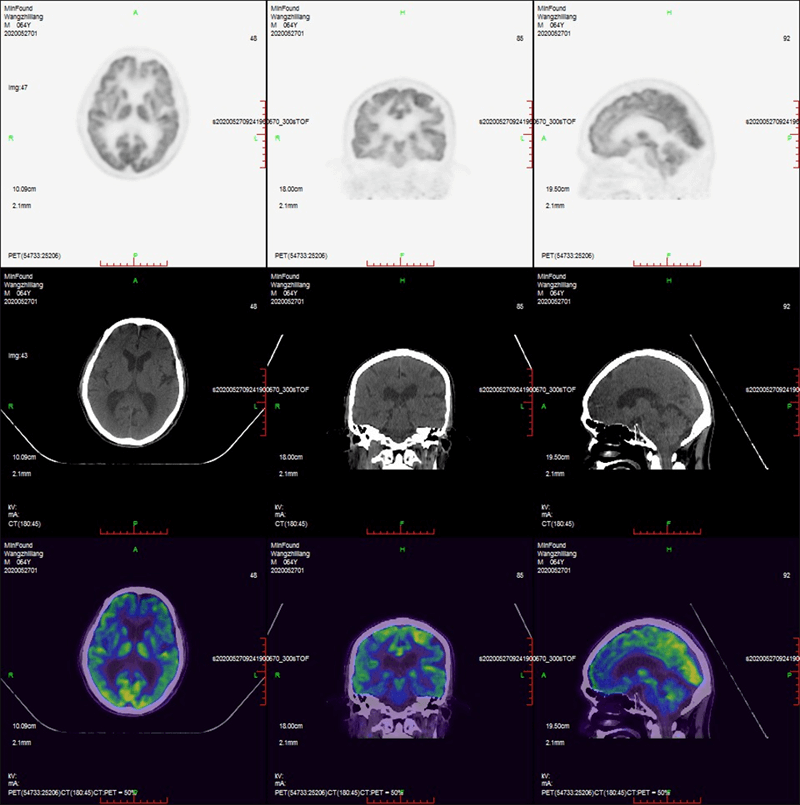

Clinical Gallery